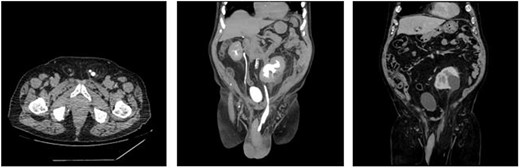

He was complaining 3 months of bilateral scrotal pain and swelling but worsening in the last 2 weeks. Computed tomography (CT) of abdomen/pelvis was performed to further investigate cystic structure in the inguinoscrotal hernia. It was reported as large left inguinoscrotal hernia containing left ureter with moderate to severe hydronephrosis and mild inferior lateral traction on right ureter (Figure 1a, 1b and 1c). Patient did not present with any bowel obstruction symptoms. Initial blood test was unremarkable with Wcc 6 × 109/L, CRP 3, Urea 6.4 mmol/L and Cr 75 umol/L.

(a) Axial view of CT urogram showing left ureter folding on itself in the left inguinal canal. (b) Coronal view of CT urogram showing moderate-to-severe hydronephrosis and hydroureter of left kidney. (c) Coronal view of CT abdomen-pelvis showing peritoneal contents pulled into the large left inguinoscrotal hernia.